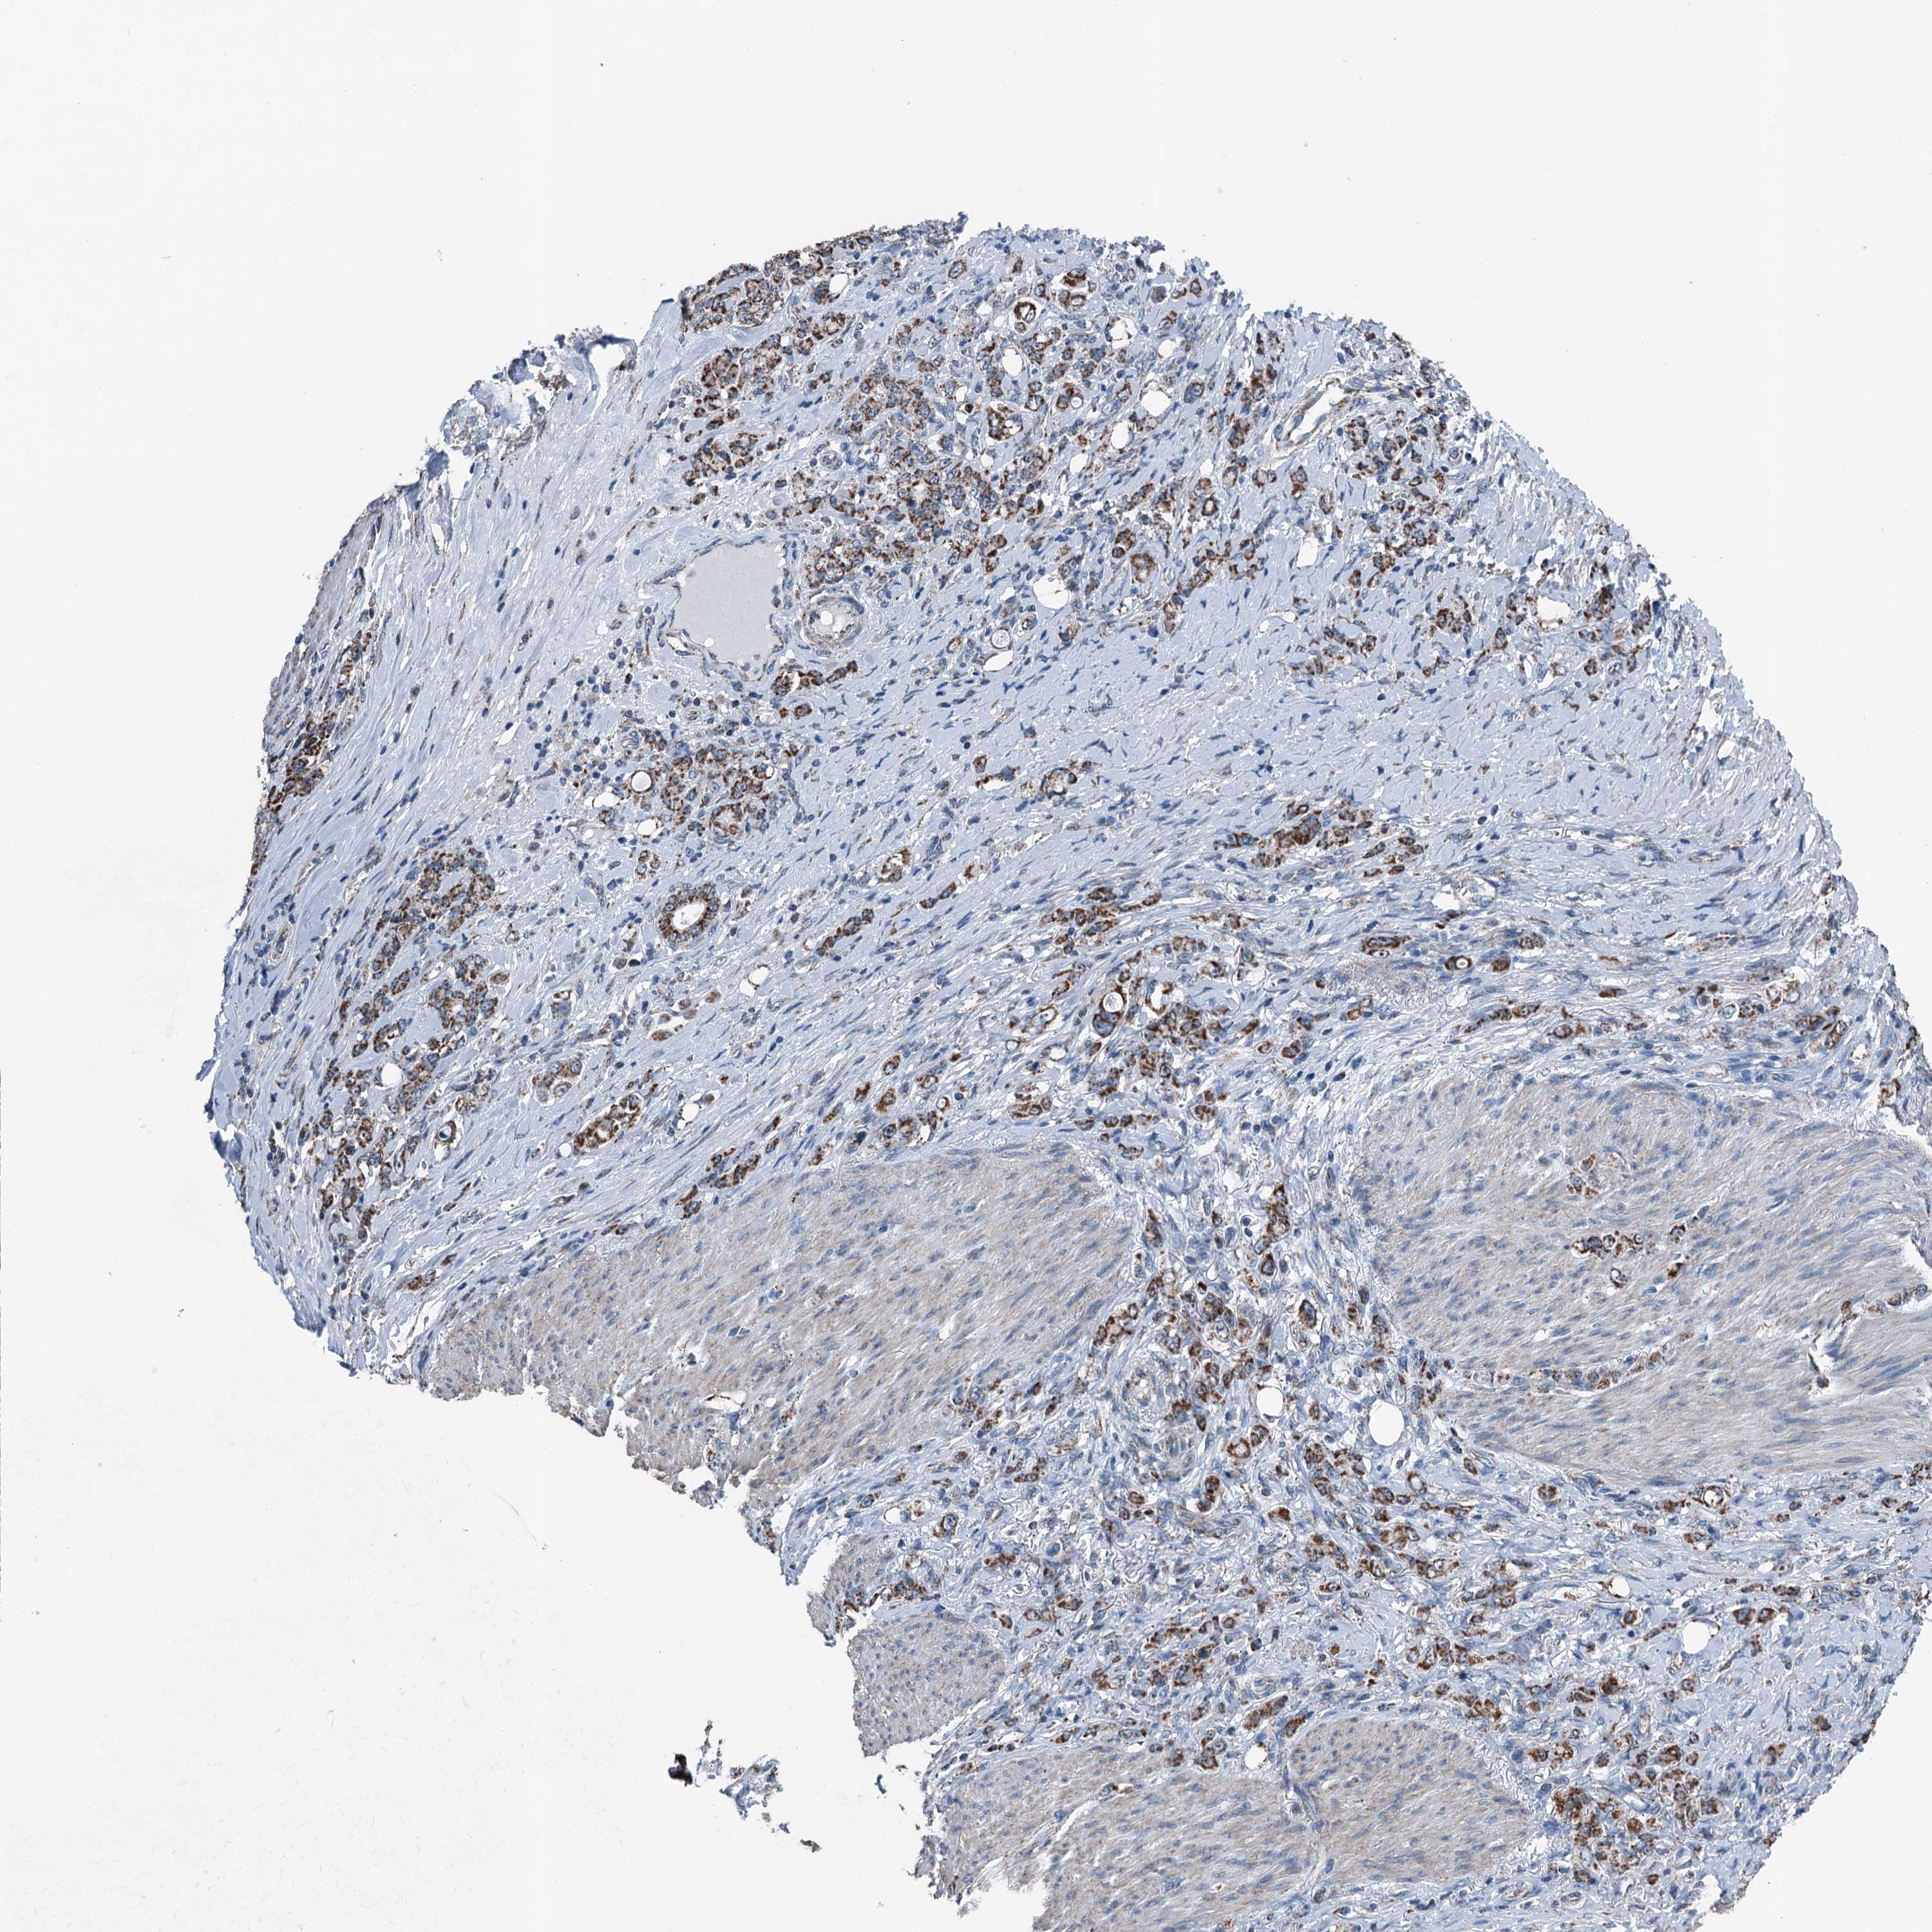

STOMACH CANCER - Protein expressioni

A mouse-over function shows sample information and annotation data. Click on an image to view it in a full screen mode. Samples can be filtered based on level of antibody staining by selecting one or several of the following categories: high, medium, low and not detected. The assay and annotation is described here.

Note that samples used for immunohistochemistry by the Human Protein Atlas do not correspond to samples in the TCGA dataset.

Antibody stainingi

Antibody staining in the annotated cell types in the current human tissue is reported as not detected, low, medium, or high, based on conventional immunohistochemistry profiling in selected tissues. This score is based on the combination of the staining intensity and fraction of stained cells.

Each image is clickable and will lead to virtual microscopy that enables deeper exploration of all samples and also displays staining intensity scores, fraction scores and subcellular localization as well as patient and tissue information for each sample.

Antibody HPA038705

Antibody HPA038706

Staining

High

Medium

Low

Not detected

Intensity

Strong

Moderate

Weak

Negative

Quantity

>75%

75%-25%

<25%

None

Location

Nuclear

Cytoplasmic/membranous

Cytoplasmic/membranous,nuclear

Adenocarcinoma, NOS

Adenocarcinoma, High grade